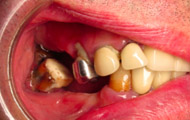

Exemple de 3 dents manquantes remplacées par 3 couronnes sur implants.

Pose des piliers prothétiques et des 3 couronnes scellées.